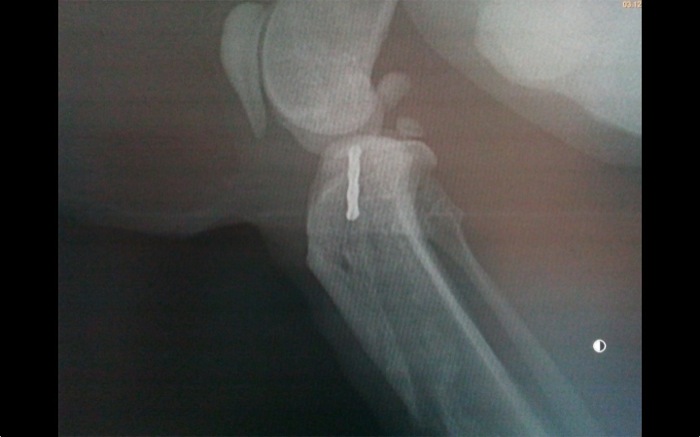

La posición laterolateral nos da el detalle de lo que está pasando. A pesar de esto hay cierta movilidad de flexión de unos 30º.

El animal se mantuvo dentro de casa y se limitó en lo posible su movilidad sobre todo en alturas pero aparece al mes y medio de la intervención con este desplazamiento. Aunque la inmovilización de la rodilla se pensó para dos meses se decide liberar la articulación y valorar. Algunos autores recomiendan esperar entre 6 y 8 semanas.

En quirófano tras retirar el clavo tenemos una rodilla con movilidad disminuida en la flexión-extensión pero estable ante cualquier movilidad lateral o de rotación. La evolución no ha presentado complicaciones y ya en la revisión a las 48 h tenemos una buena evolución con un gato que se desplaza en consulta con igual destreza en ambos miembros posteriores.